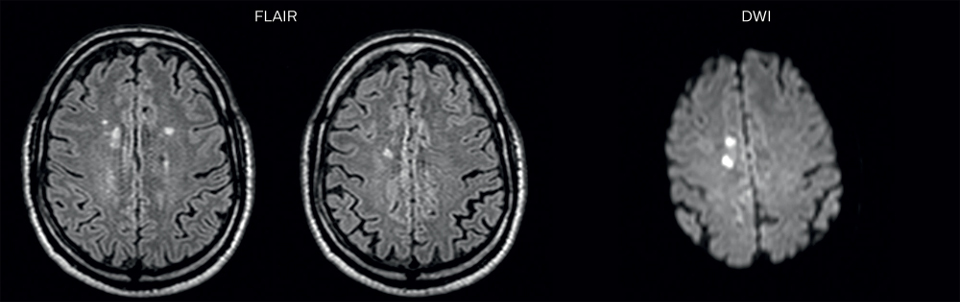

On FLAIR images we can see some nonspecific high signal abnormalities in frontal white matter bilaterally. On DWI we can see acute ischemic lesions which appear with high signal intensity. Arrows show vessel wall enhancement which appears concentric and homogeneous in different cerebral territories.

Arrows show vessel wall enhancement which appears concentric and homogeneous in different cerebral territories.

On the routine MR sequences that we did, we could see acute

ischemic lesions. We see them very well on the diffusion images,

where acute ischemic lesions usually appear with high signal

intensity and restricted diffusion. However, the etiology of these

lesions cannot be derived from these images.